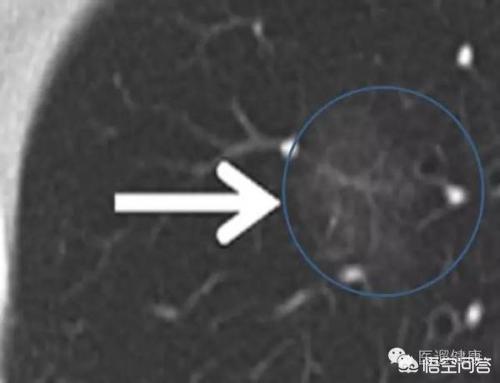

对于没有完全钙化的肺结节,如果直径在1cm以上,就有可能需要手术。虽然一部分磨玻璃样结节的确与肺癌相关,但大多数其实与炎症有关。对于直径在8毫米以上的结节,如果经济条件允许,建议做PET-CT......

对于直径在1cm以上的肺结节,如果患者本身存在一些高危因素,一是穿刺活检,判断到底是良性还是恶性的,另一种是直接手术切除。对于远离中央支气管的外周型结节,均可以考虑做穿刺活检。对于影像学特征不明显的可......